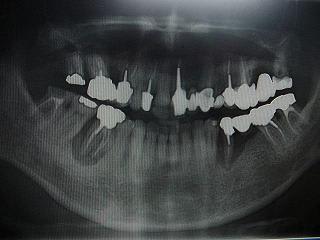

voici un cas paro qui me pose problème: Homme 39 ans, non fumeur, exellente santé ( spotif +++). PAJ dans un mauvais contexte occlusal ( bout à bout et contact essentiellement en posterieur. Je suis un peu paumé sur ce coup là! surtout sur le devenir des molaires. Des pistes avant d'en parler à nice? merci

Je ne suis pas sûr de voir une PAJ avec les destructions dentaires visibles à la pano.

D'autant que sur tes rétro la lésion évolue autour d'une dent, la 46, de façon évidente alors que 47 n'a pas bougé.

comme ressace toujours phil, la pano ne suffit pas, il faut un bilan long cone ( ha, ha!). C'est vrai et dans ce cas, on voit très mal une méga poche en M et P de 17. les poches sur 17, 35 et 46 suintent la danette un max...

En fait, je me gourre, j' ai parlé de PAJ un peu vite, il faut que je revois avec lui, entre autre la cause de perte des dents.